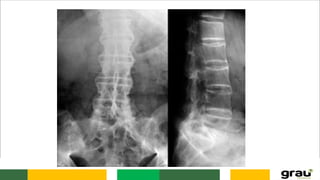

Coluna Vertebral

CURVATURAS: Primárias e secundarias

IMPORTÂNCIA CLINICA: hipercifose, hiperlordose escoliose

IMAGEM PANORÂMICA DA COLUNA !

COLUNA VERTEBRAL CURVATURAS: Primáriase secundarias IMPORTÂNCIA CLINICA: hipercifose, hiperlordose escoliose Caracteristicas das vértebras permitem identificar a que região pertencem.